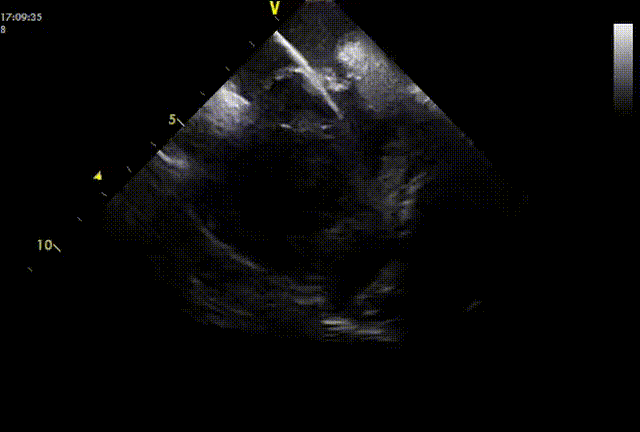

图片

导丝通过PFO